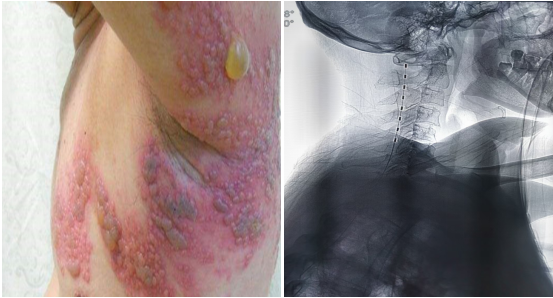

脊髓神经电刺激植入术(六)

脊髓神经电刺激植入术是指将脊髓刺激电极置于椎管的硬膜外腔后间隙,刺激电极产生电场,刺激脊髓后部的上行结构:脊神经背根、脊髓后角神经元、脊髓丘脑束等,通过电流刺激脊髓后柱的传导束和后角感觉神经元,阻断/干扰疼痛信号通过脊髓向大脑传递,从而达到治疗疼痛或其它疾病目的的一种治疗方法。电刺激植入的适应症: 复杂性局灶性疼痛综合征(CRPS) 、神经源性疼痛(神经病理性疼痛) 、幻肢痛/残肢痛、带状疱疹后遗神经痛、脊髓损伤 、 糖尿病周围神经痛、周围缺血性疼痛 、血栓闭塞性脉管炎、糖尿病足等慢性疼痛。

神经电刺激术的优点:

1.微创技术,非破坏性、可逆性、并发症少;

2.可根据病人的需要调节电压、脉宽、频率;

3.可通过测试刺激评估疗效,避免不必要的手术;

4.是目前国际上公认的治疗慢性顽固性疼痛的先进疗法。